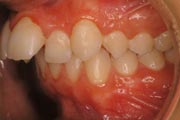

Crowding

After